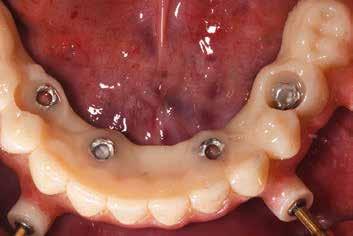

Klinikánkon egy teljesen fogatlan, hagyományos akrilát fogpótlással helyreállított 65 éves férfi beteg jelentkezett, aki nem kielégítő alsó fogsorretencióra és az azzal járó problémákra panaszkodott, beleértve a kifejezetten az alsó fogsorához kapcsolódó gyenge beszéd és rágásfunkciót. A klinikai vizsgálat gömbölyűtől a késhegyig terjedő mandibulagerinc formát és megfelelő vertikális, de nem megfelelő vízszintes csontmennyiséget állapított meg, különösen a hátsó területen (1. ábra) 10

A hagyományos teljes kivehető fogpótlási technikákkal a kezelési stratégia a felső és alsó állcsont kapcsolatának és az okkluzális vertikális dimenzió és a fog helyzetének meghatározását foglalta magában, majd az alsó rögzített restauráció előállításához ezeket használták fel referenciákként (3. ábra) 11